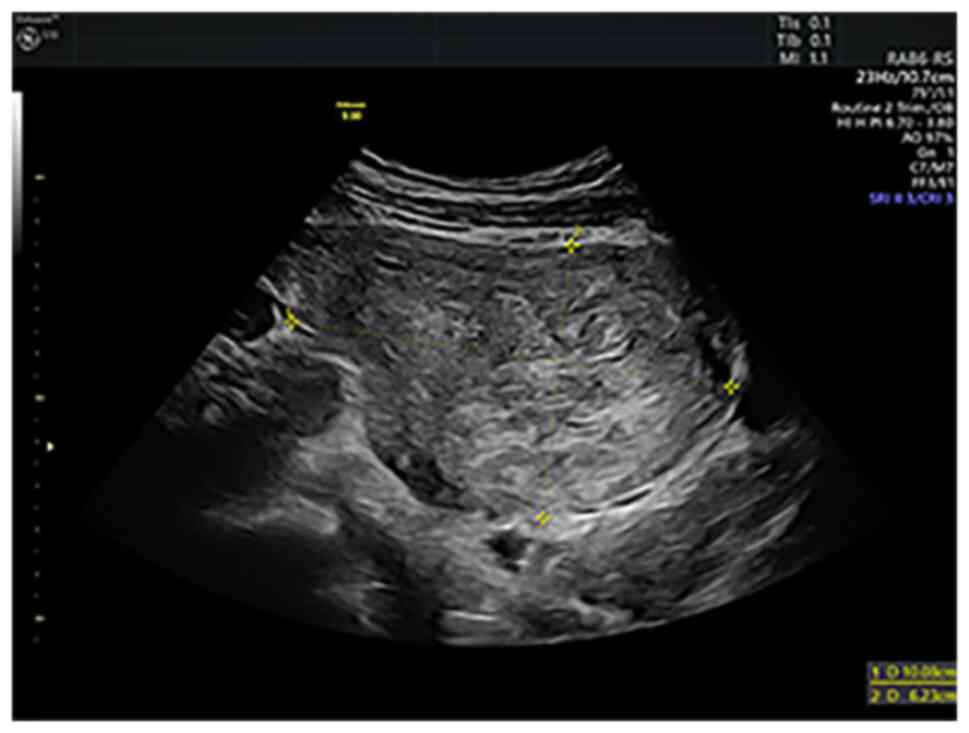

Upon admission, the ultrasound examination revealed a 10-cm anterior intramural and subserosal uterine leiomyoma without unusual features, but there were other ultrasound findings suggestive of adenomyosis in the posterior uterine wall (Figs. 1 and 2). After counseling, the patient opted for a total abdominal hysterectomy with bilateral salpingectomy and conservation of both ovaries to prevent the effects of estrogenic privation. Due to the localization of the myoma towards the broad ligament, its dimensions, and the suspected adenomyosis, it was decided to proceed with open surgery. The intervention itself was undertaken without difficulties and complications. The patient made a favorable postsurgical recovery and was discharged after 4 days of hospitalization.

Gray scale ultrasound aspect of the 10 cm fibroid.

Doppler ultrasound evaluation of the 10 cm fibroid.